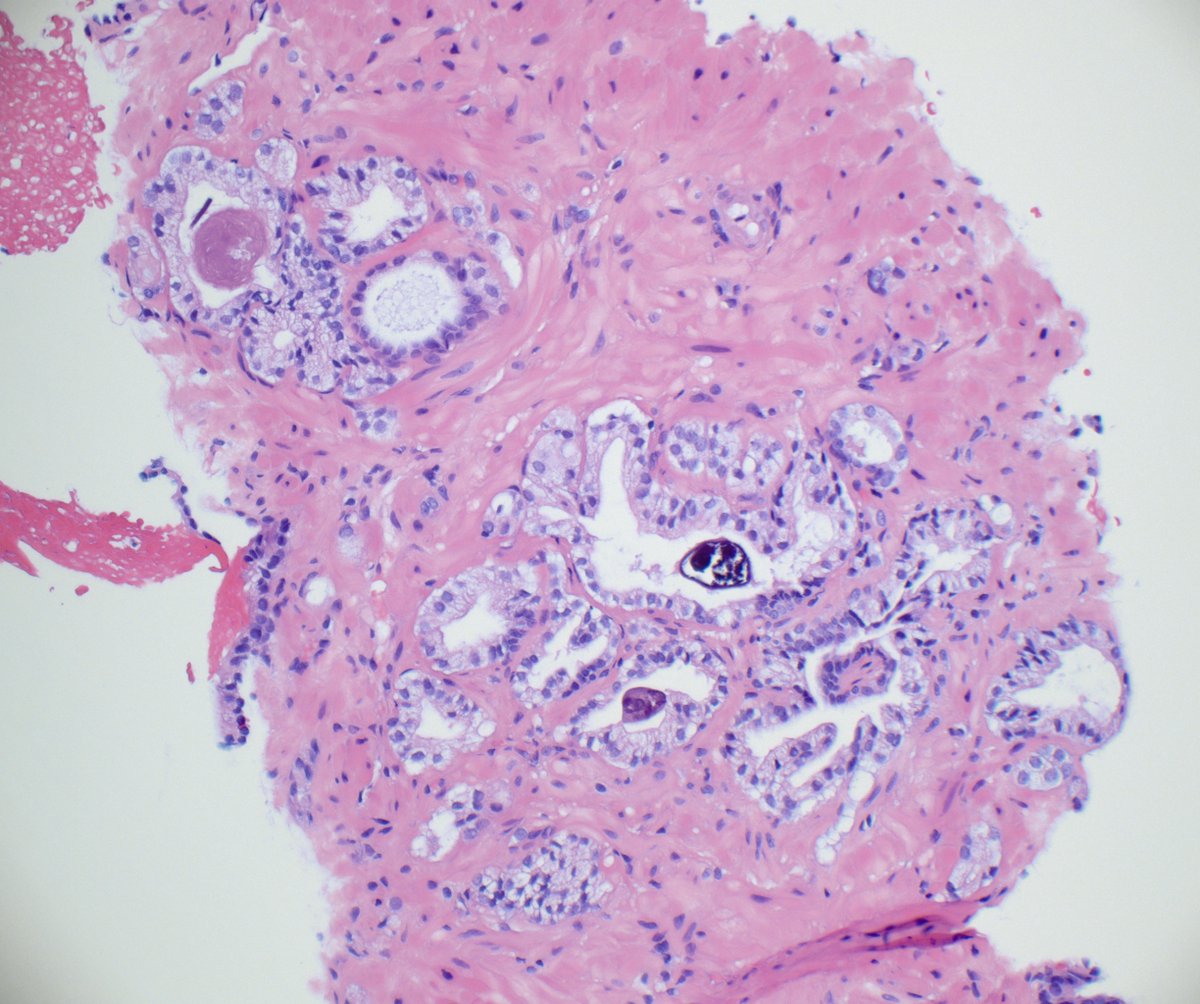

Indeed this is amebic colitis! Uncommon in western world (h/o travel is important). Characteristic flask shaped ulcers, amebic trophozoites often with ingested RBCs. #pathboards

Not my typical #gupath #gynpath post but an interesting one for trainees! Colon biopsy for GI bleed, clinical concern for IBD. #pathboards

0

15

63